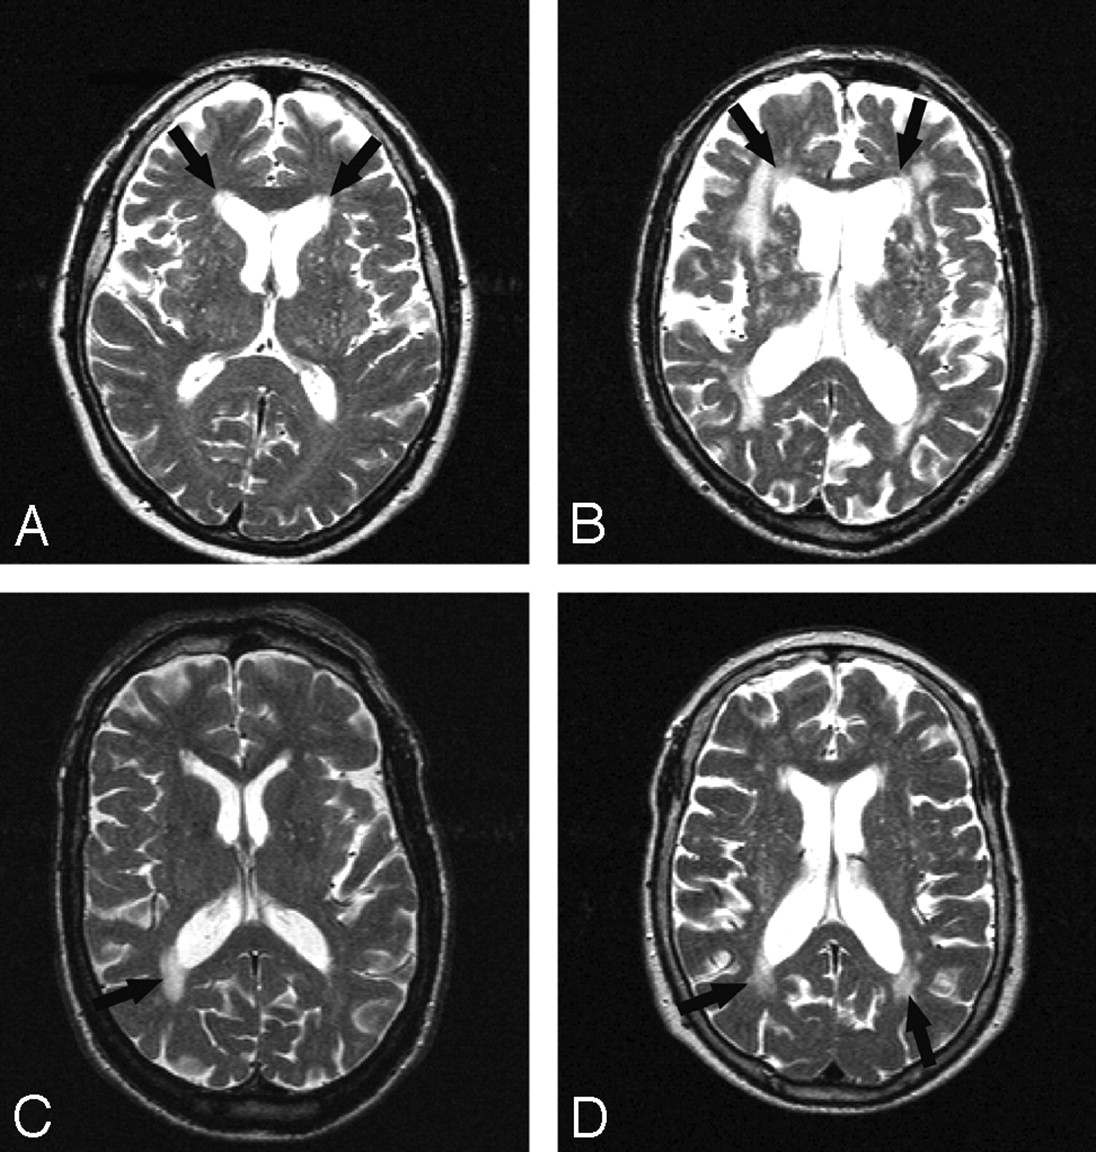

Periventricular lesions were detected and classified in irregular or smooth lesions (Fig 1), according to Fazekas et al.10 “Smooth delineation” was defined as having a smooth outline with normal-appearing white matter in all sections showing the PVWMH. Left and right PVWMH were considered separately. The classification of PVWMH was assessed in a consensus meeting by 3 of the authors (M.A.V.B., R.G., and A.S.). This was done for occipital and frontal periventricular lesions separately by using T2-weighted, proton density (PD), and FLAIR images. On T1-weighted images, the presence of periventricular hypointense lesions was assessed (Fig 2). They were defined as lesions with signal intensities on T1-weighted images lower than those of the surrounding white matter but higher than those of CSF.

Different types of PVWMH. Examples of frontal PVWMH with a smooth lining (A, right and left) and frontal PVWMH with an irregular lining (B, right and left) and examples of occipital PVWMH with smooth (C, right) and irregular (D, right and left) linings.